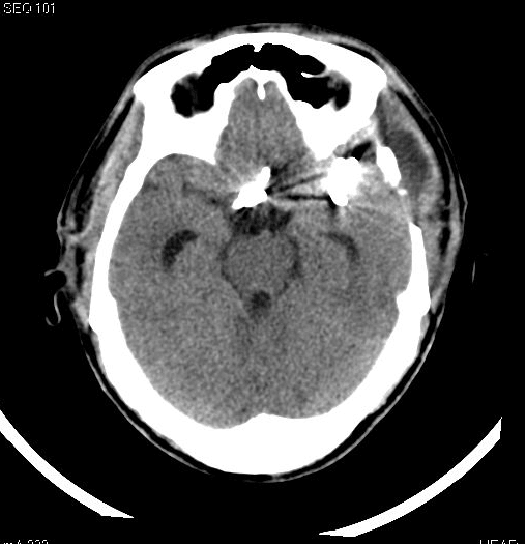

术后吴先生神志清醒, 10天后复查造影影像显示:颅内多发动脉瘤夹闭术后改变,右侧大脑中动脉M1起始部动脉瘤、前交通动脉瘤、左侧大脑中动脉分叉处动脉瘤均未显影,载瘤动脉通畅,无明显狭窄。

▲术后CT